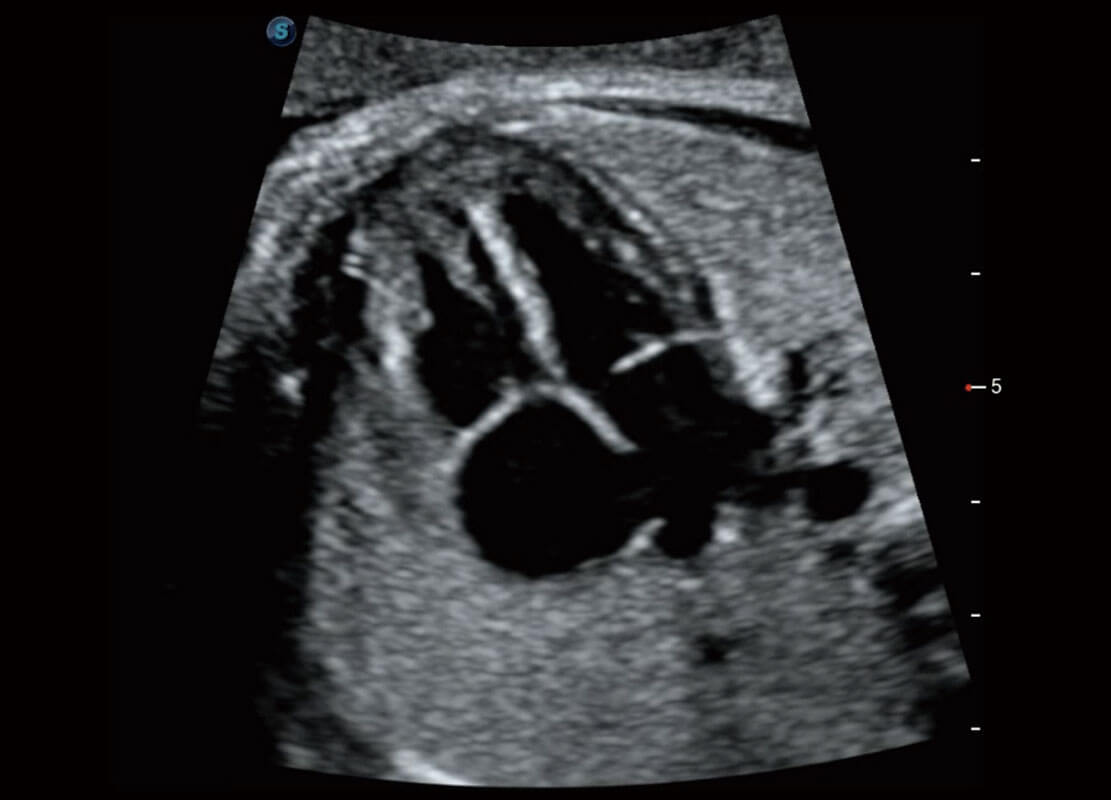

P60提供简单易学易用的高端诊断工具,为您中晚孕筛查提供快速清晰的解剖信息。

S-Fetus能够助您在实时扫查过程中自动识别标准切面、自动测量并录入报告。一个按键,即可快速、高效地获取胎儿生理指标,简化您的产科检查操作。